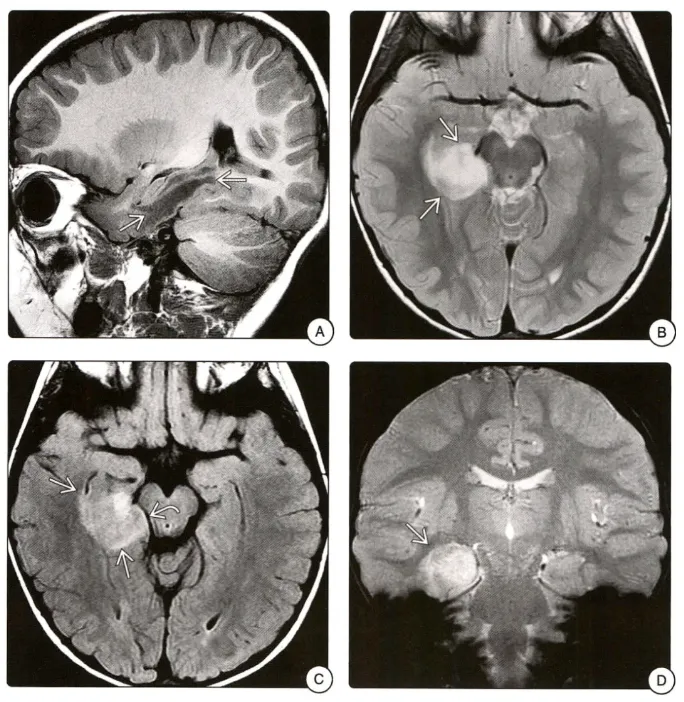

在大脑皮层,血管中心性胶质瘤通常位于颞叶或额叶。脑干病例也有报道。在MRI上,这些肿瘤通常边界清楚,无对比增强,在T2加权和FLAIR图像上呈高信号。在某些病例中,T1加权MRI上肿瘤周围存在边缘样高信号。茎状延伸至相邻侧脑室和营养不良性钙化是其他可变特征。

图A矢状位T1WI可见右侧颞叶低信号肿块。B轴位T1WI图像显示右侧颞叶边界欠清的高信号肿块。C FLAIR序列图像上病变呈高信号,并轻度肿胀,压迫邻近中脑。D冠状位T2*WI图像显示病变内未见提示钙化或出血的低信号。